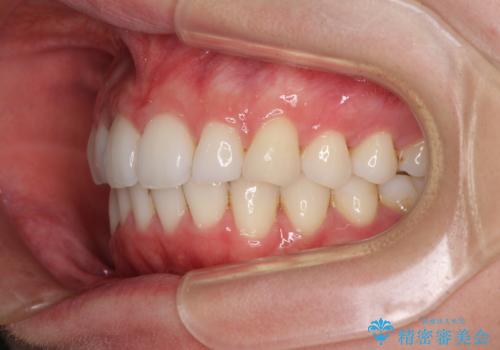

- 上下前歯の叢生を気にして来院された患者様です。

以前矯正をした後戻りということで、歯列不正はそれほど大きくなかったため、インビザライン・ライトを用いて矯正治療を行うこととしました。

前歯のデコボコが残っており、シミュレーション通りに動いていない部分がありましたが、再矯正であることやご本人の満足いくところまでデコボコが改善されたとのことで、治療を終了することとしました。